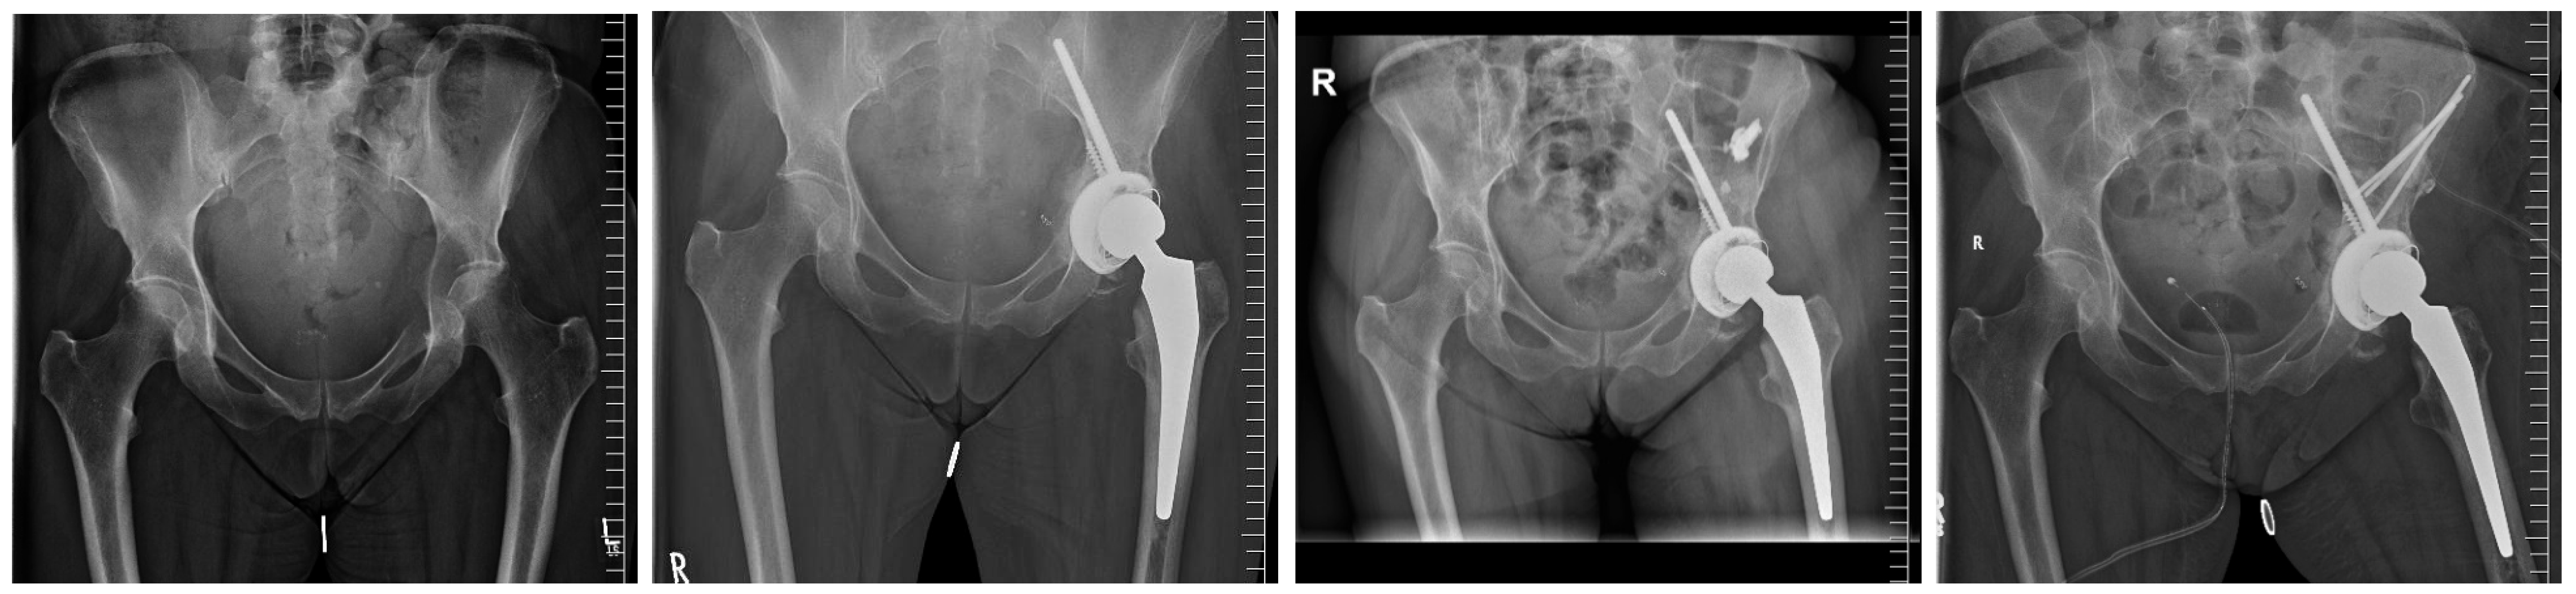

The Modified Harrington Procedure for Metastatic Peri-Acetabular Bone Lesion Using a Novel Highly Porous Titanium Revision Shell with Long Lever Arm Screw

2.2. Surgical Procedure

3.4. Complications